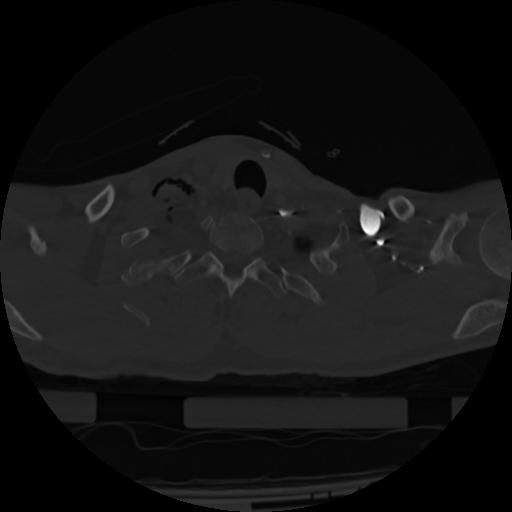

22 ANGIO,CE,Vol,0.5,ANGIO,,